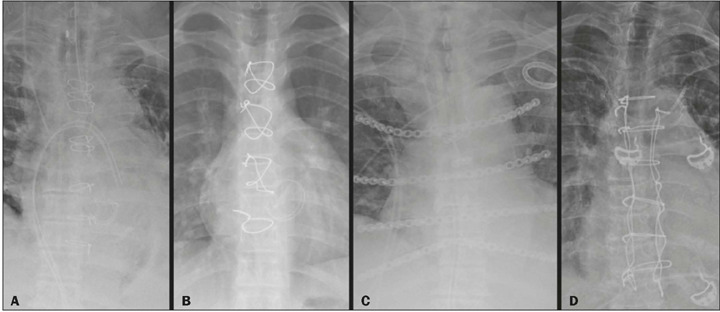

A typical approach for many cardiovascular surgical procedures is median sternotomy. Despite advances in surgical techniques and postoperative care, complications still occur in 0.5-5.0% of cases. Radiological assessment of the chest after sternotomy is a challenge, because normal findings resulting from surgical trauma can resemble complications. This pictorial essay aims to provide an overview of normal postoperative imaging findings and the spectrum of complications that can arise, including surgical material-related issues, hematomas, bone complications, and infections. Diagnosis and management require careful interpretation of imaging studies, considering the recovery timeline and clinical status of the patient. With the increasing number of cardiothoracic surgical procedures, this is essential knowledge for radiologists, allowing them to contribute to an accurate diagnosis and the appropriate management of patients.